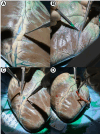

Methods: Porcine arrested hearts (n = 18) were used to evaluate territorial distribution of native coronary arteries and of a coronary bypass constructed with porcine saphenous vein graft (SVG) using ICG. Coronary ostia were dissected and selectively cannulated for ICG injection. Sequential fluorescence was assessed in the epicardial coronary arteries, myocardium and coronary veins using an infrared-sensitive charge-coupled device (CCD) camera system. In a separate set of experiments, SVG was used for anastomosis in end-to-side fashion to a terminal obtuse marginal (OM) branch. This approach was used to avoid bias in the assessment of territorial distribution. The anastomosis was injected with ICG; graft patency and territorial distribution was assessed using an infrared-sensitive CCD camera system from 30 cm above the field, as previously described. Native circulation and SVG grafts were assessed using real-time video recording and fluorescence intensity mapping that was averaged into a graded scoring system. The heart was divided into functional regions: anterior wall, lateral wall, inferior wall and right ventricle. All experiments were performed in triplicates.

Results: After ICG injection into the individual coronary ostia, perfusion of the native coronary artery was visible. Portions of the vessels embedded into the epicardial fat could be easily visualized on the surface of the heart and the dissection facilitated via fluorescence guidance. The territorial distribution reflected the expected regional perfusion. The SVG graft was anastomosed to an OM branch. ICG visualization allowed for assessment of graft patency excluding potential technical anastomosis problems or graft twisting or dissection. The myocardial perfusion observed in real-time confirmed regional distribution to the entire lateral wall and minimally to the inferior wall. These findings were confirmed in all the specimens used in the study.